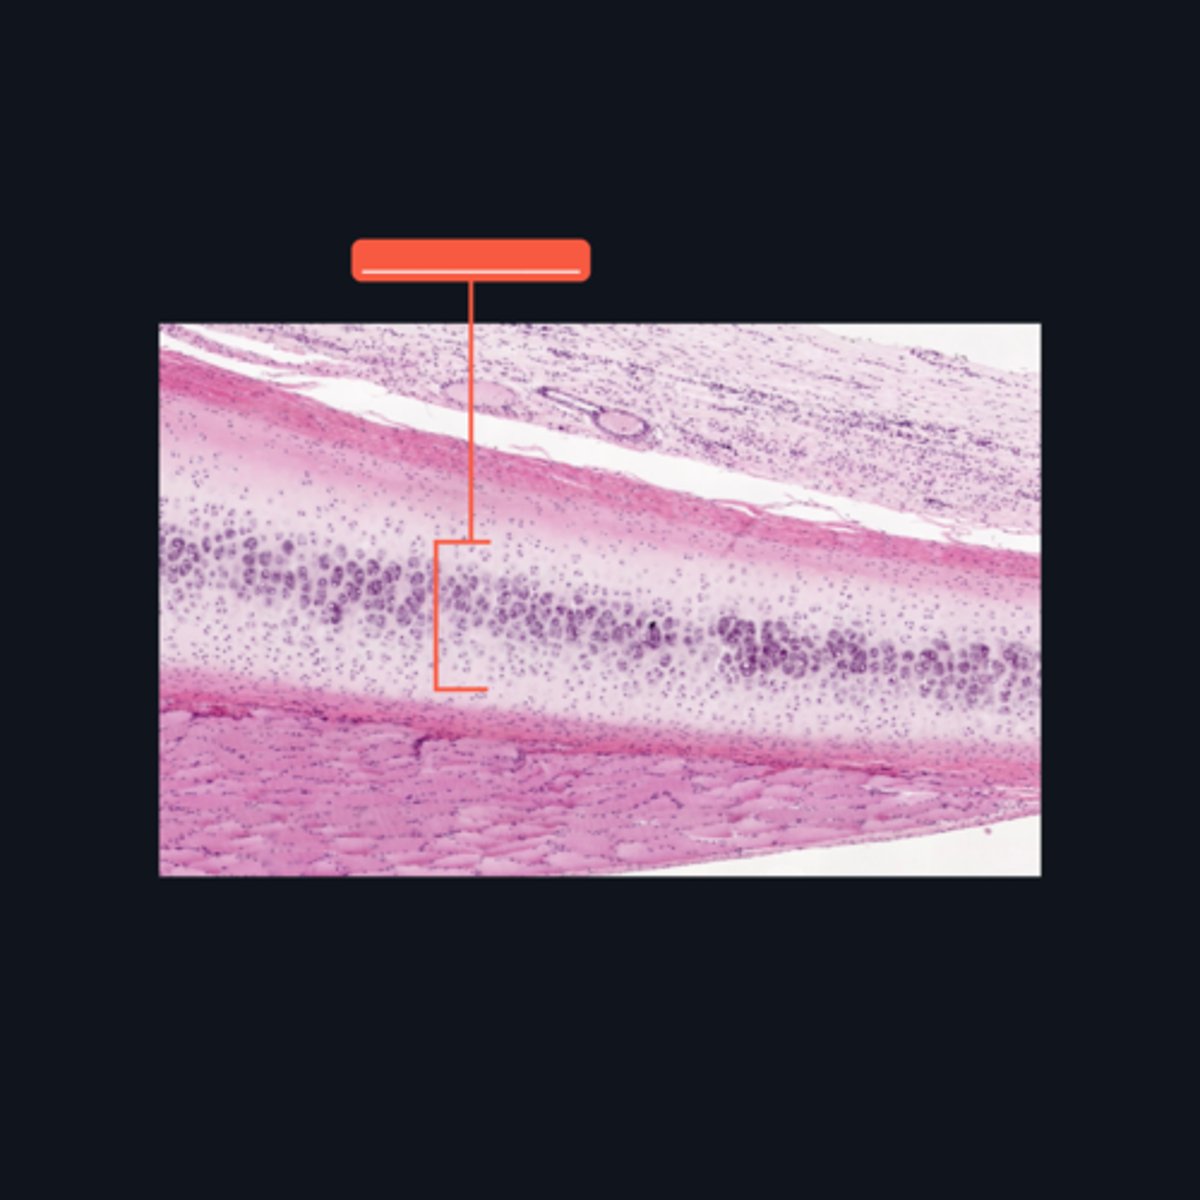

Epiphyseal Plate

Identify the pointed structure

End of the increase in length of bone

What signifies the closure of the pointed structure?

A - Zone of Resting Cartilage Cells

B - Zone of Proliferation

C - Zone of Maturation

D - Zone of Calcification

E - Zone of Ossification

Identify the pointed structures

B - Zone of Proliferation

Which pointed structure is the zone where instestitial growth occurs and what zone is it?

E - Zone of Ossification

Which pointed structure and what zone where many of the cavities left by cartilage cells merge to form marrow cavities?

C - Zone of Maturation

Which pointed structure and what zone do not divide anymore?

A - Zone of Resting Cartilage Cells

Which pointed structure and what zone anchors the epiphyseal plate to the epiphysis?

D - Zone of Calcification

Which pointed structure and what zone where the cartilage matrix is calcified